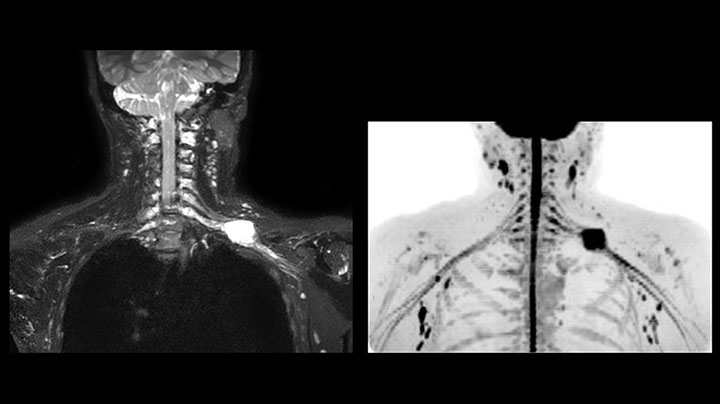

This patient is a 43-year-old female with a left supraclavicular nerve sheath tumor. The lesion is well visualized on the STIR VISTA images and on the MR neurography using DWIBS. The exam was performed on Prodiva 1.5T.

Acq voxel size 1.2 x 1.3 x 2.4 mm, Recon voxel size 0.7 x 0.7 x 1.2 mm, dS SENSE factor 2, scan time 5:46 min.